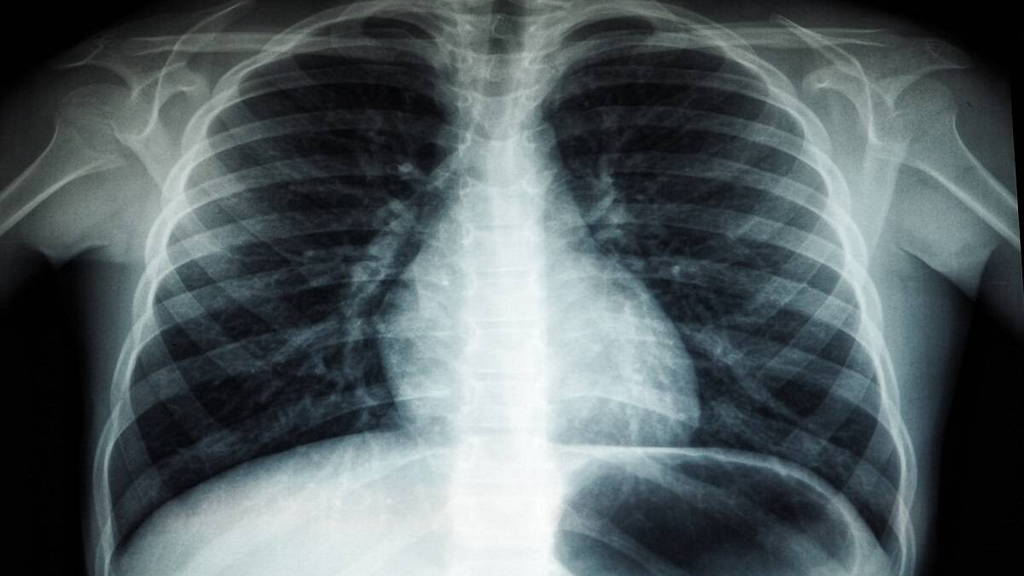

Door artsen gebruik te laten maken van zogenoemde C-bogen, die eruitzien als een letter C, kunnen artsen röntgenbeelden maken tijdens een behandeling, zodat zij goed kunnen zien wat ze in het lichaam doen. Dit is mogelijk door röntgenstraling en nucleaire beeldvorming samen te voegen.

Bij behandelingen van sommige soorten kanker, maar ook bijvoorbeeld bij cardiologische ingrepen, zou het nuttig kunnen zijn om naast beeldvorming met röntgenstraling tegelijk ook nucleaire beeldvorming te realiseren. Daarbij wordt gebruik gemaakt van oplichtende radioactieve stoffen in het lichaam. Nucleaire beeldvorming is vooral geschikt om het functioneren van organen in beeld te brengen, zoals de bloedstroom door het hart of de stofwisseling in de hartspier.

Klinisch fysici van de afdeling Radiologie en Nucleaire Geneeskunde van het UMC Utrecht hebben de afgelopen jaren een hybride C-boog ontwikkeld waarmee tegelijkertijd röntgen- en nucleaire beelden gemaakt kunnen worden.

“Tot op dit moment was het niet mogelijk röntgenstraling en nucleaire beeldvorming samen te voegen voor gebruik in een behandelkamer,” zegt Hugo de Jong, klinisch fysicus in het UMC Utrecht. “De twee technieken veilig en effectief combineren bleek mogelijk met een gepatenteerde dubbellaags detector. Eerder hebben we deze innovatie al succesvol klinisch getest bij een specifieke kankerbehandeling: radio-embolisatie van de lever.”